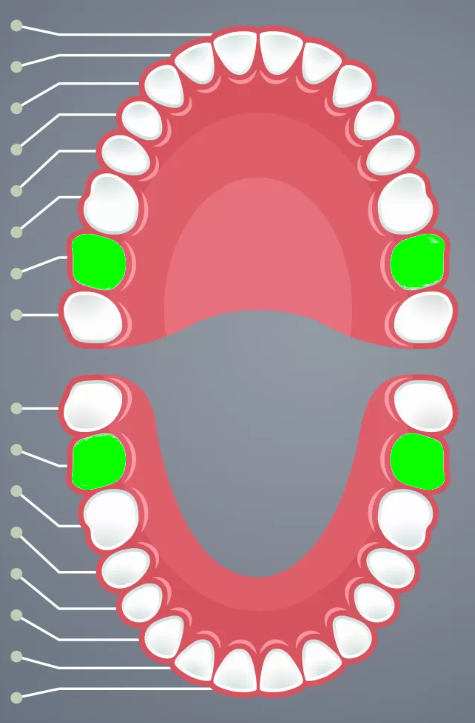

Incisors

Cuspids

Bicuspids

2nd molars

3rd molars